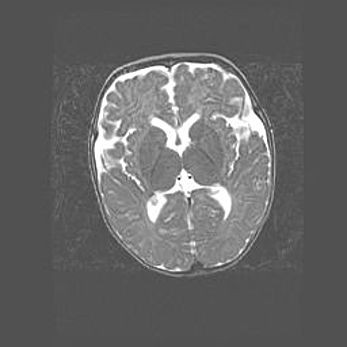

Церебральная ишемия II.

Возраст: 5 дней

Вес: 3400 г

Пол: женский

Окружность головы: 35 см

Срок гестации: 39 недель

Церебральная ишемия – это заболевание, характеризующееся недостаточностью (гипоксией) либо полным прекращением (аноксией) снабжения мозга кислородом по причине закупорки одного или нескольких сосудов. Это приводит к  что метаболическим расстройствам различной степени тяжести в тканях головного мозга, развитию коагуляционных некрозов и гибели нейронов.